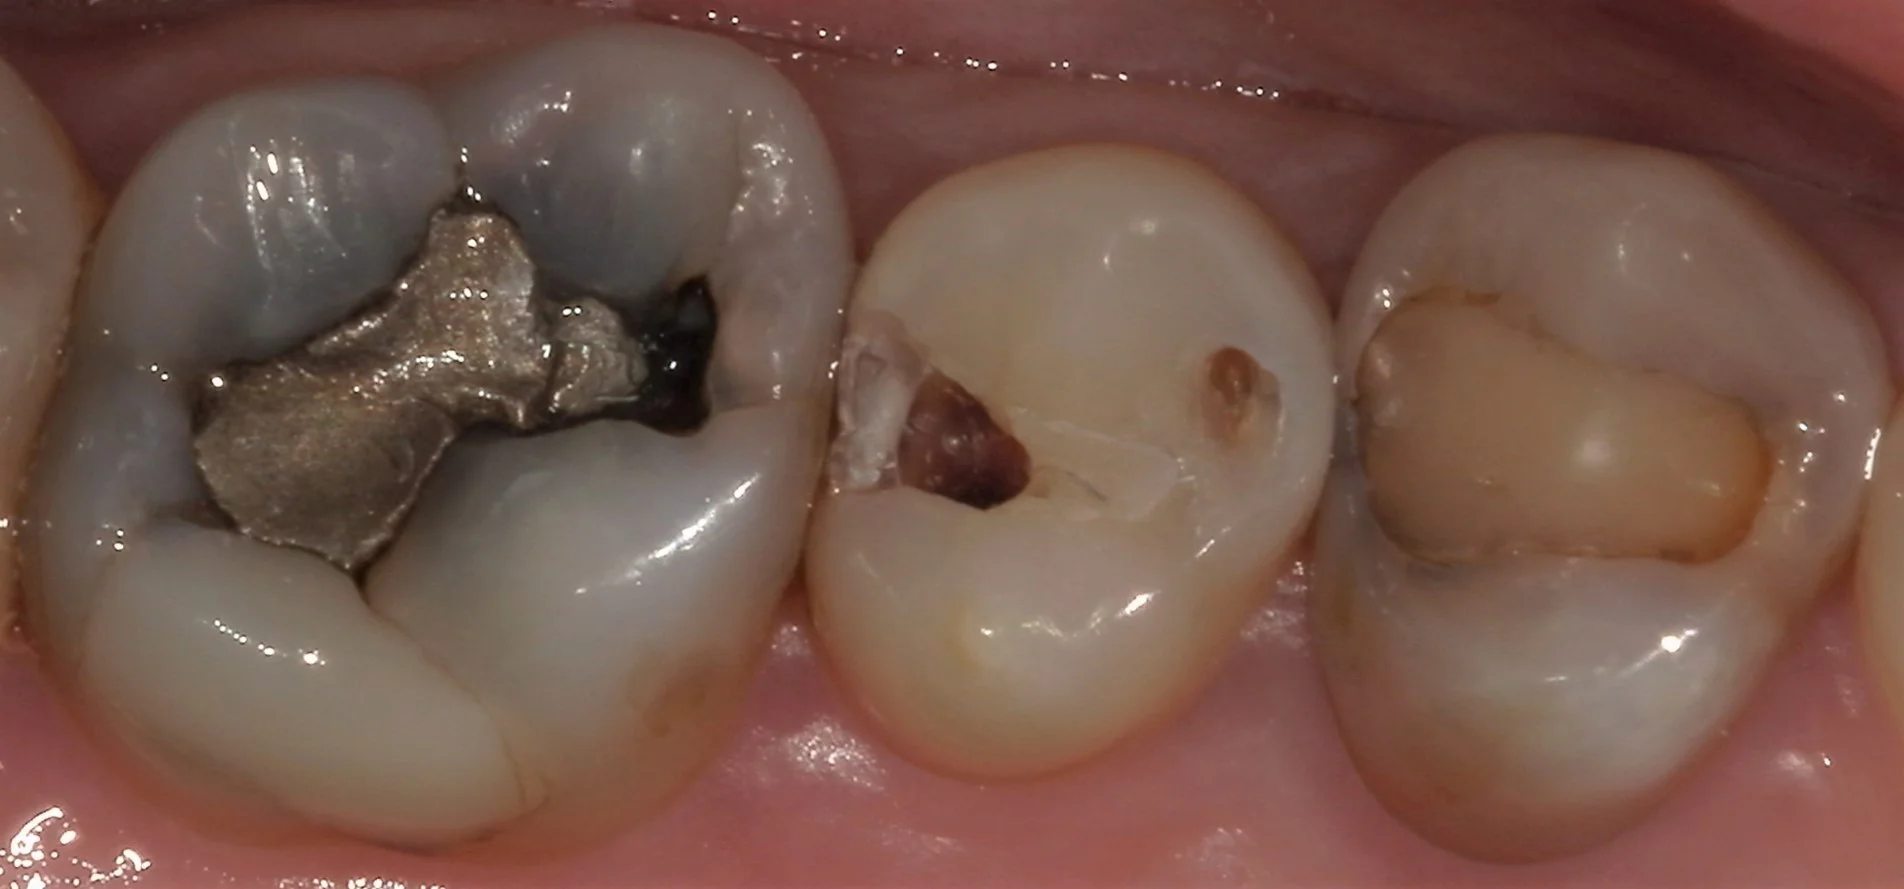

まず古い詰め物を取って虫歯を見やすくしたのが、こちらです。

こう見るとかなり内面が黒く虫歯になっているのが分かるかと思います。

前後の歯の間にまで進行していましたので、そこら辺も全部除去したのがこちらです。